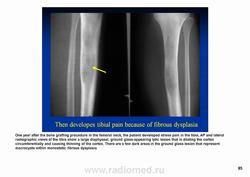

Фиброзная дисплазия — заболевание, характеризующееся нарушением развития (дисплазия) скелета, при котором нормальная кость замещается фиброзной тканью с элементами диспластически изменённой кости. Выделяют монооссальную (около 85% случаев), мономелическую (поражено несколько соседних костей одной конечности, плечевого или тазового пояса) и полиоссальную (около 5% случаев) формы. Фиброзная дисплазия как аномалия развития иногда сочетается с внескелетными расстройствами: 1) полиоссальная форма поражения сочетается с преждевременным половым созреванием и пигментными пятнами на коже в виде кофейных пятен (Albright’s syndrome); 2) сочетание фиброзной дисплазии с миксомами мягких тканей (Mazabraud’s syndrome). Встречается в любом возрасте, наиболее часто в первые 3 десятилетия жизни (70% больных). Монооссальная форма несколько чаще встречается у лиц мужского пола, при полиоссальной форме соотношение лиц мужского и женского пола 2 : 1. Поражается любая кость, наиболее частая локализация: проксимальная часть бедренной кости, большеберцовая и плечевая кости, рёбра, кости черепа, шейного отдела позвоночника. Поражение костей позвоночника только в 2,5% случаев.